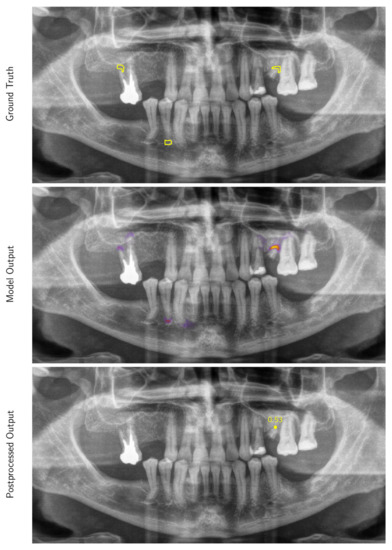

3.2. Performance of the Deep Learning Algorithm